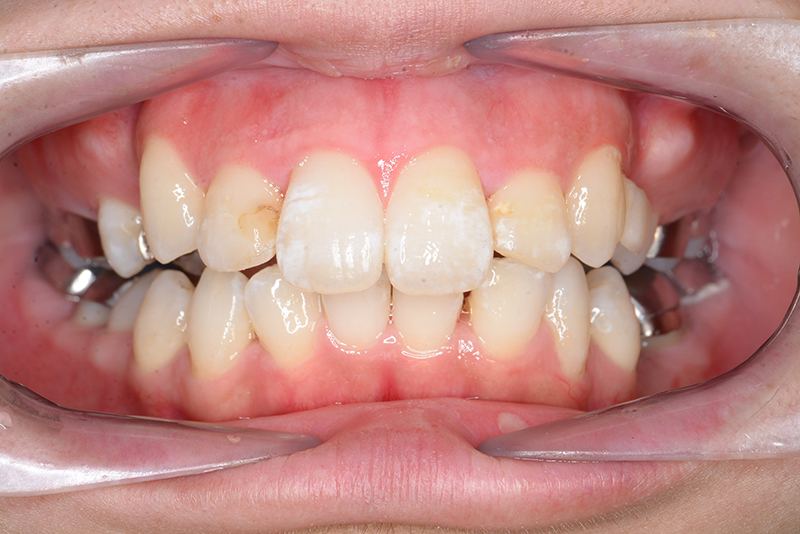

動的治療中のIOP(治療開始後6ヶ月)

動的治療中のIOP

(治療開始後6ヶ月)

動的治療中のIOP(治療開始後12ヶ月)

(治療開始後12ヶ月)